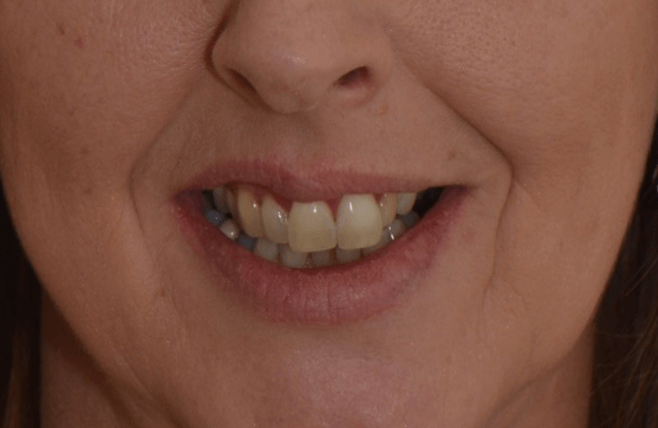

For example, in this case the centrals are parallel with color differences and the laterals are distally inclined. This causes visual tension in the smile composition: